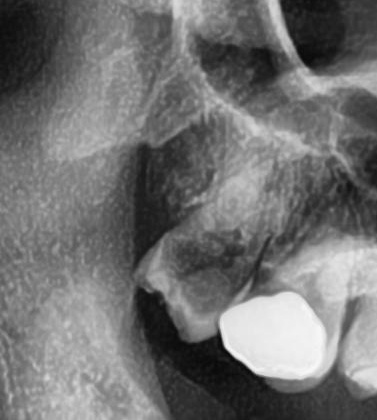

パノラマ写真を撮影してみると、右上の親知らずは手前の歯と並んでまっすぐ生えているのが確認できました。

今回は上顎洞からも距離があるため、抜歯は可能と診断されました。